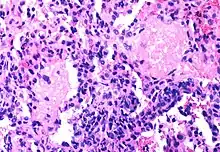

Most AIDS symptoms result from the development of opportunistic infections and cancers associated with severe immunosuppression secondary to HIV.

The diseases associated with AIDS, such as Pneumocystis jiroveci pneumonia (PCP) and Mycobacterium avium complex (MAC), are not caused by HIV, but rather result from the immunosuppression caused by HIV disease. As the immune system of an HIV-infected individual weakens, he or she becomes susceptible to the particular viral, fungal, and bacterial infections common in the community. For example, HIV-infected people in the Midwestern United States are much more likely than people in New York City to develop histoplasmosis, which is caused by a fungus. A person in Africa is exposed to pathogens different from individuals in an American city. Children may be exposed to different infectious agents compared to adults.[89]

HIV is the underlying cause of the condition named AIDS, but the additional conditions that may affect an AIDS patient are dependent upon the endemic pathogens to which the patient may be exposed.